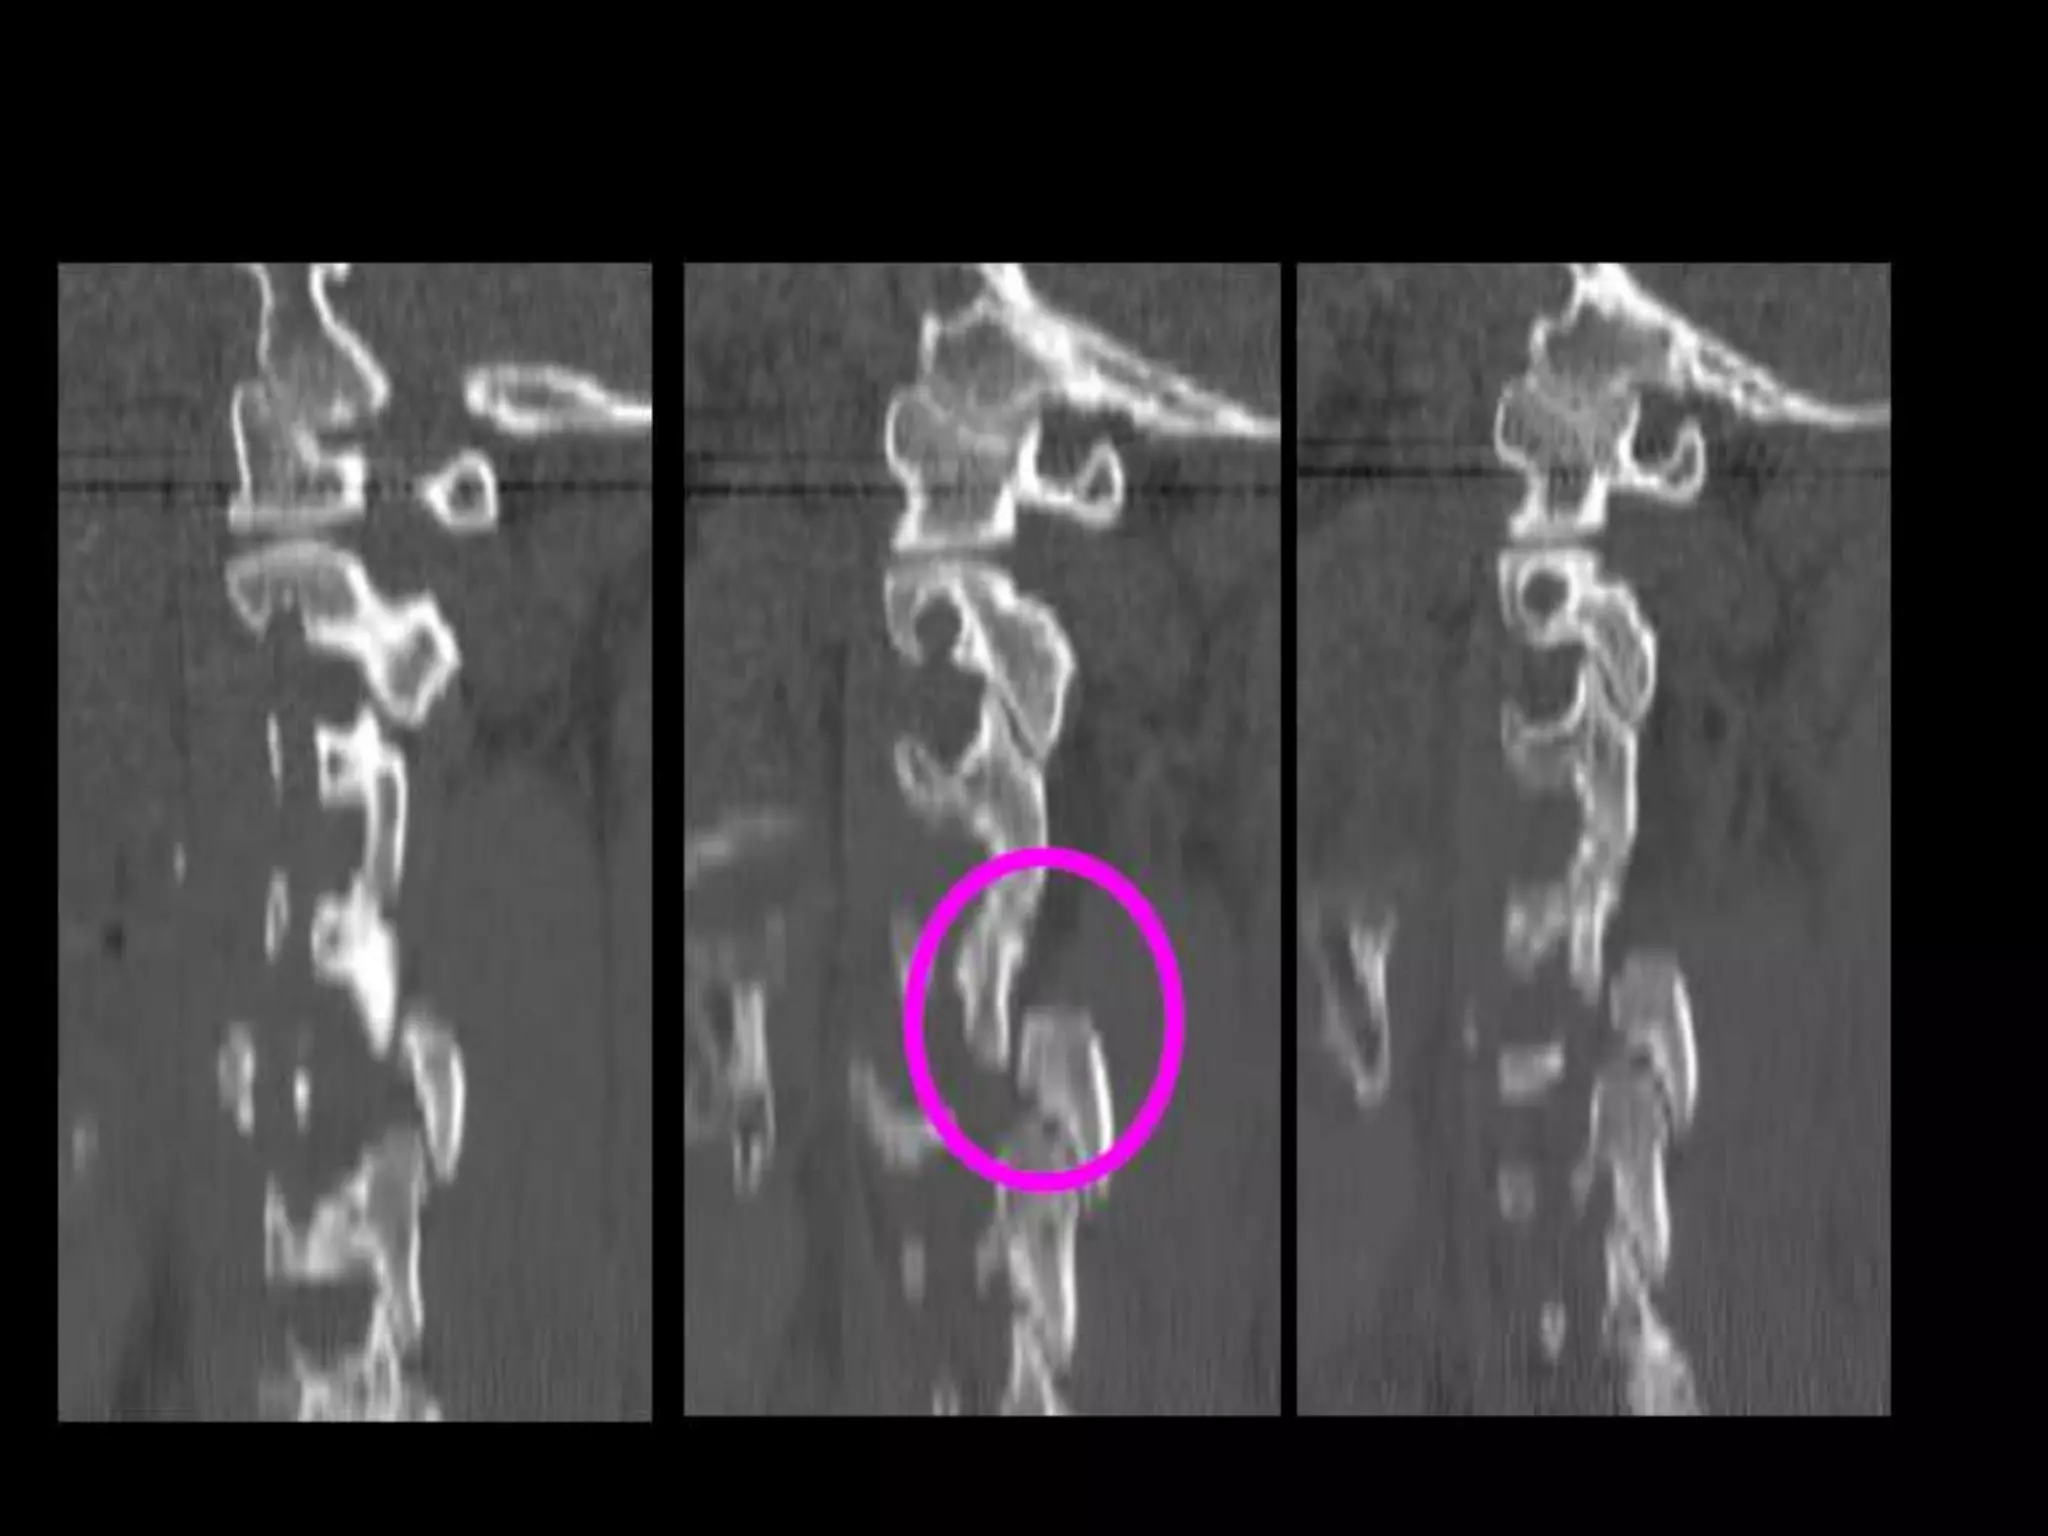

Odontoid (Dens) Fractures:

• 11-13% c-spine injuries (up to 27% in some

series).

– 75% of cases are children.

• Classification

– Anderson & D’Alonzo (I, II and III).

• Associations

– atlantoaxial dislocations.

– Jefferson FX.

• Radiography may be subtle.

• Prevertebral STS nasopharynx.